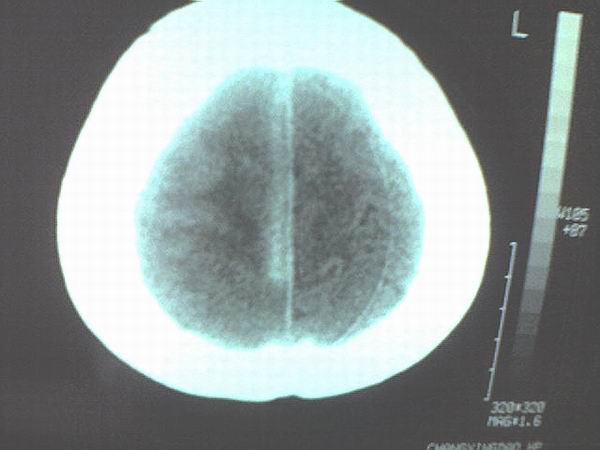

标题: CT12572:女 43岁 头痛恶心呕吐两天请求会诊 [打印本页]

女 43岁 头痛恶心呕吐两天

手机照的,不是太清楚。

右侧大脑镰硬膜下出血

1、右侧大脑镰硬膜下出血2、机器伪影太重,该修修。